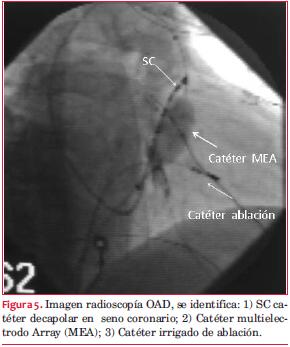

Se utilizaron tres catéteres: a) irrigado para ablación, Biotronik®; b) decapolar en seno coronario, y c) catéter multielectrodo Array (MEA) en VD. Se realiza anticoagulación con heparina sódica controlada en forma seriada manteniendo tiempo de coagulación activado mayor a 300 durante todo el procedimiento. El modo Array genera el campo eléctrico a partir del catéter multipolar y un parche situado en la zona abdominal. MEA es un catéter 9 French, con longitud de 110 cm, con lumen interno y extremo distal en forma de balón de 7,5 ml con terminación atraumática en formato pigtail. El balón contiene una malla de acero inoxidable que proporciona 64 microelectrodos y tres electrodos de localización por encima de la malla y dos por debajo. Desde el amplificador del sistema EnSite se envía una señal que es detectada por los electrodos MEA y devuelta al amplificador donde se procesa. El sistema representa señales unipolares virtuales de la zona que rodea al catéter, que son generadas sin necesidad de que exista contacto físico entre catéter y tejido. El sistema es capaz de adquirir hasta 3.000 registros virtuales unipolares. El modo Array permite realizar la cartografía con un solo latido(3).

Se posiciona el catéter balón a nivel de tracto de salida del ventrículo derecho (TSVD). Con catéter irrigado se realiza reconstrucción anatómica del TSVD y posteriormente se realizó cartografía sin contacto de la extrasístole (figura 3). Se topografía el foco de origen sobre el anillo tricuspídeo sector superior entre la hora 1 y 2 en proyección oblicua anterior izquierda y considerando la válvula tricúspide como un reloj. A 1 cm del registro de potencial de His. La precocidad conseguida en registro unipolar fue de 50 ms con respecto al inicio del QRS (figura 2). Se aplica radiofrecuencia con catéter irrigado (40 Watts, 55 grados y 60 segundos), desaparece la arritmia a los 3 segundos de iniciada la aplicación (figura 4).